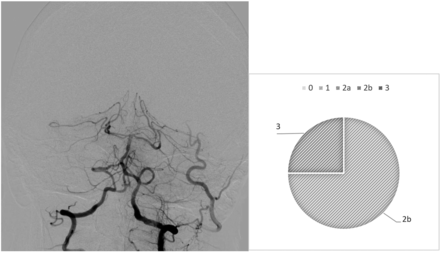

Our analysis highlights diverging behaviors from the raters: In most cases, we observed drastic variability from clusters of raters, which directly questions the existence of a defined mTICI score. For example, case 6 (Fig 1) is an occlusion of the proximal basilar artery with a bilateral fetal configuration of the posterior communicating arteries, which divided the observers. Five of 8 observers (62.5%) assigned the score 2b, 1 (12.5%) gave it a 2a, and 2 (25%) assigned it a score of 1. On the contrary, we observed examples of more consistent analyses, in which the scores were equal or close. This result is demonstrated in case 26 (Fig 2), in which a patent posterior vasculature was achieved following thrombectomy and the analysis was more consensual: mTICI 2b (75%) and 3 (25%).

Case 6. After thrombectomy, interobserver variability.